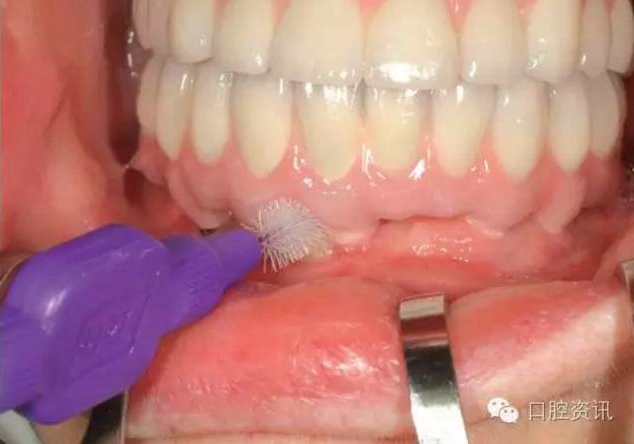

15.jpg

圖15. 使用牙線清潔

16.jpg

圖16. 使用特制的間隙刷清潔